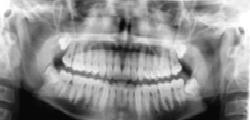

Tüm Dişler Aynı Karede

Tüm Dişler Aynı Karede Panoramik röntgen, çenelerin, tüm dişlerin, çene ve dişlerdeki bir çok rahatsızlığın tek bir filmde görülmesini sağlayan …

Panoramik röntgen, çenelerin, tüm dişlerin, çene ve dişlerdeki bir çok rahatsızlığın tek bir filmde görülmesini sağlayan röntgen filmleridir.

PANAROMİK RÖNTGEN

Panoramik röntgen neden gereklidir?

• Panoramik röntgen, çene ve dişlerde gözle görülemeyen çürük, kist ve tümör gibi oluşumların teşhisinde gereklidir.

• Tedavi planlamasının daha hızlı ve eksiksiz biçimde yapılmasına yardımcı röntgen filmleridir.

• Çene ve dişlerle ilgili operasyonlardan önce hekimin görmesi gereken bir röntgendir. Çünkü bu röntgenler tedavi uygulanacak alanı geniş bir şekilde gösterir ve operasyonun başarısını arttırır.

Dijital radyografi nedir?

Dijital radyografi; geleneksel filmler yerine sensörlerin kullanıldığı bir X-ray görüntüleme tekniğidir. Görüntüyü elde etmek için kimyasal işlemlere gerek kalmaz. Böylece zamandan tasarruf sağlanır. Aynı zamanda görüntü dijital ortamda rahatça transfer edilebilir. Konvansiyonel radyografilere göre daha az radyasyonla daha iyi kalitede görüntü elde edilebilmesi ise diğer önemli bir avantajıdır.